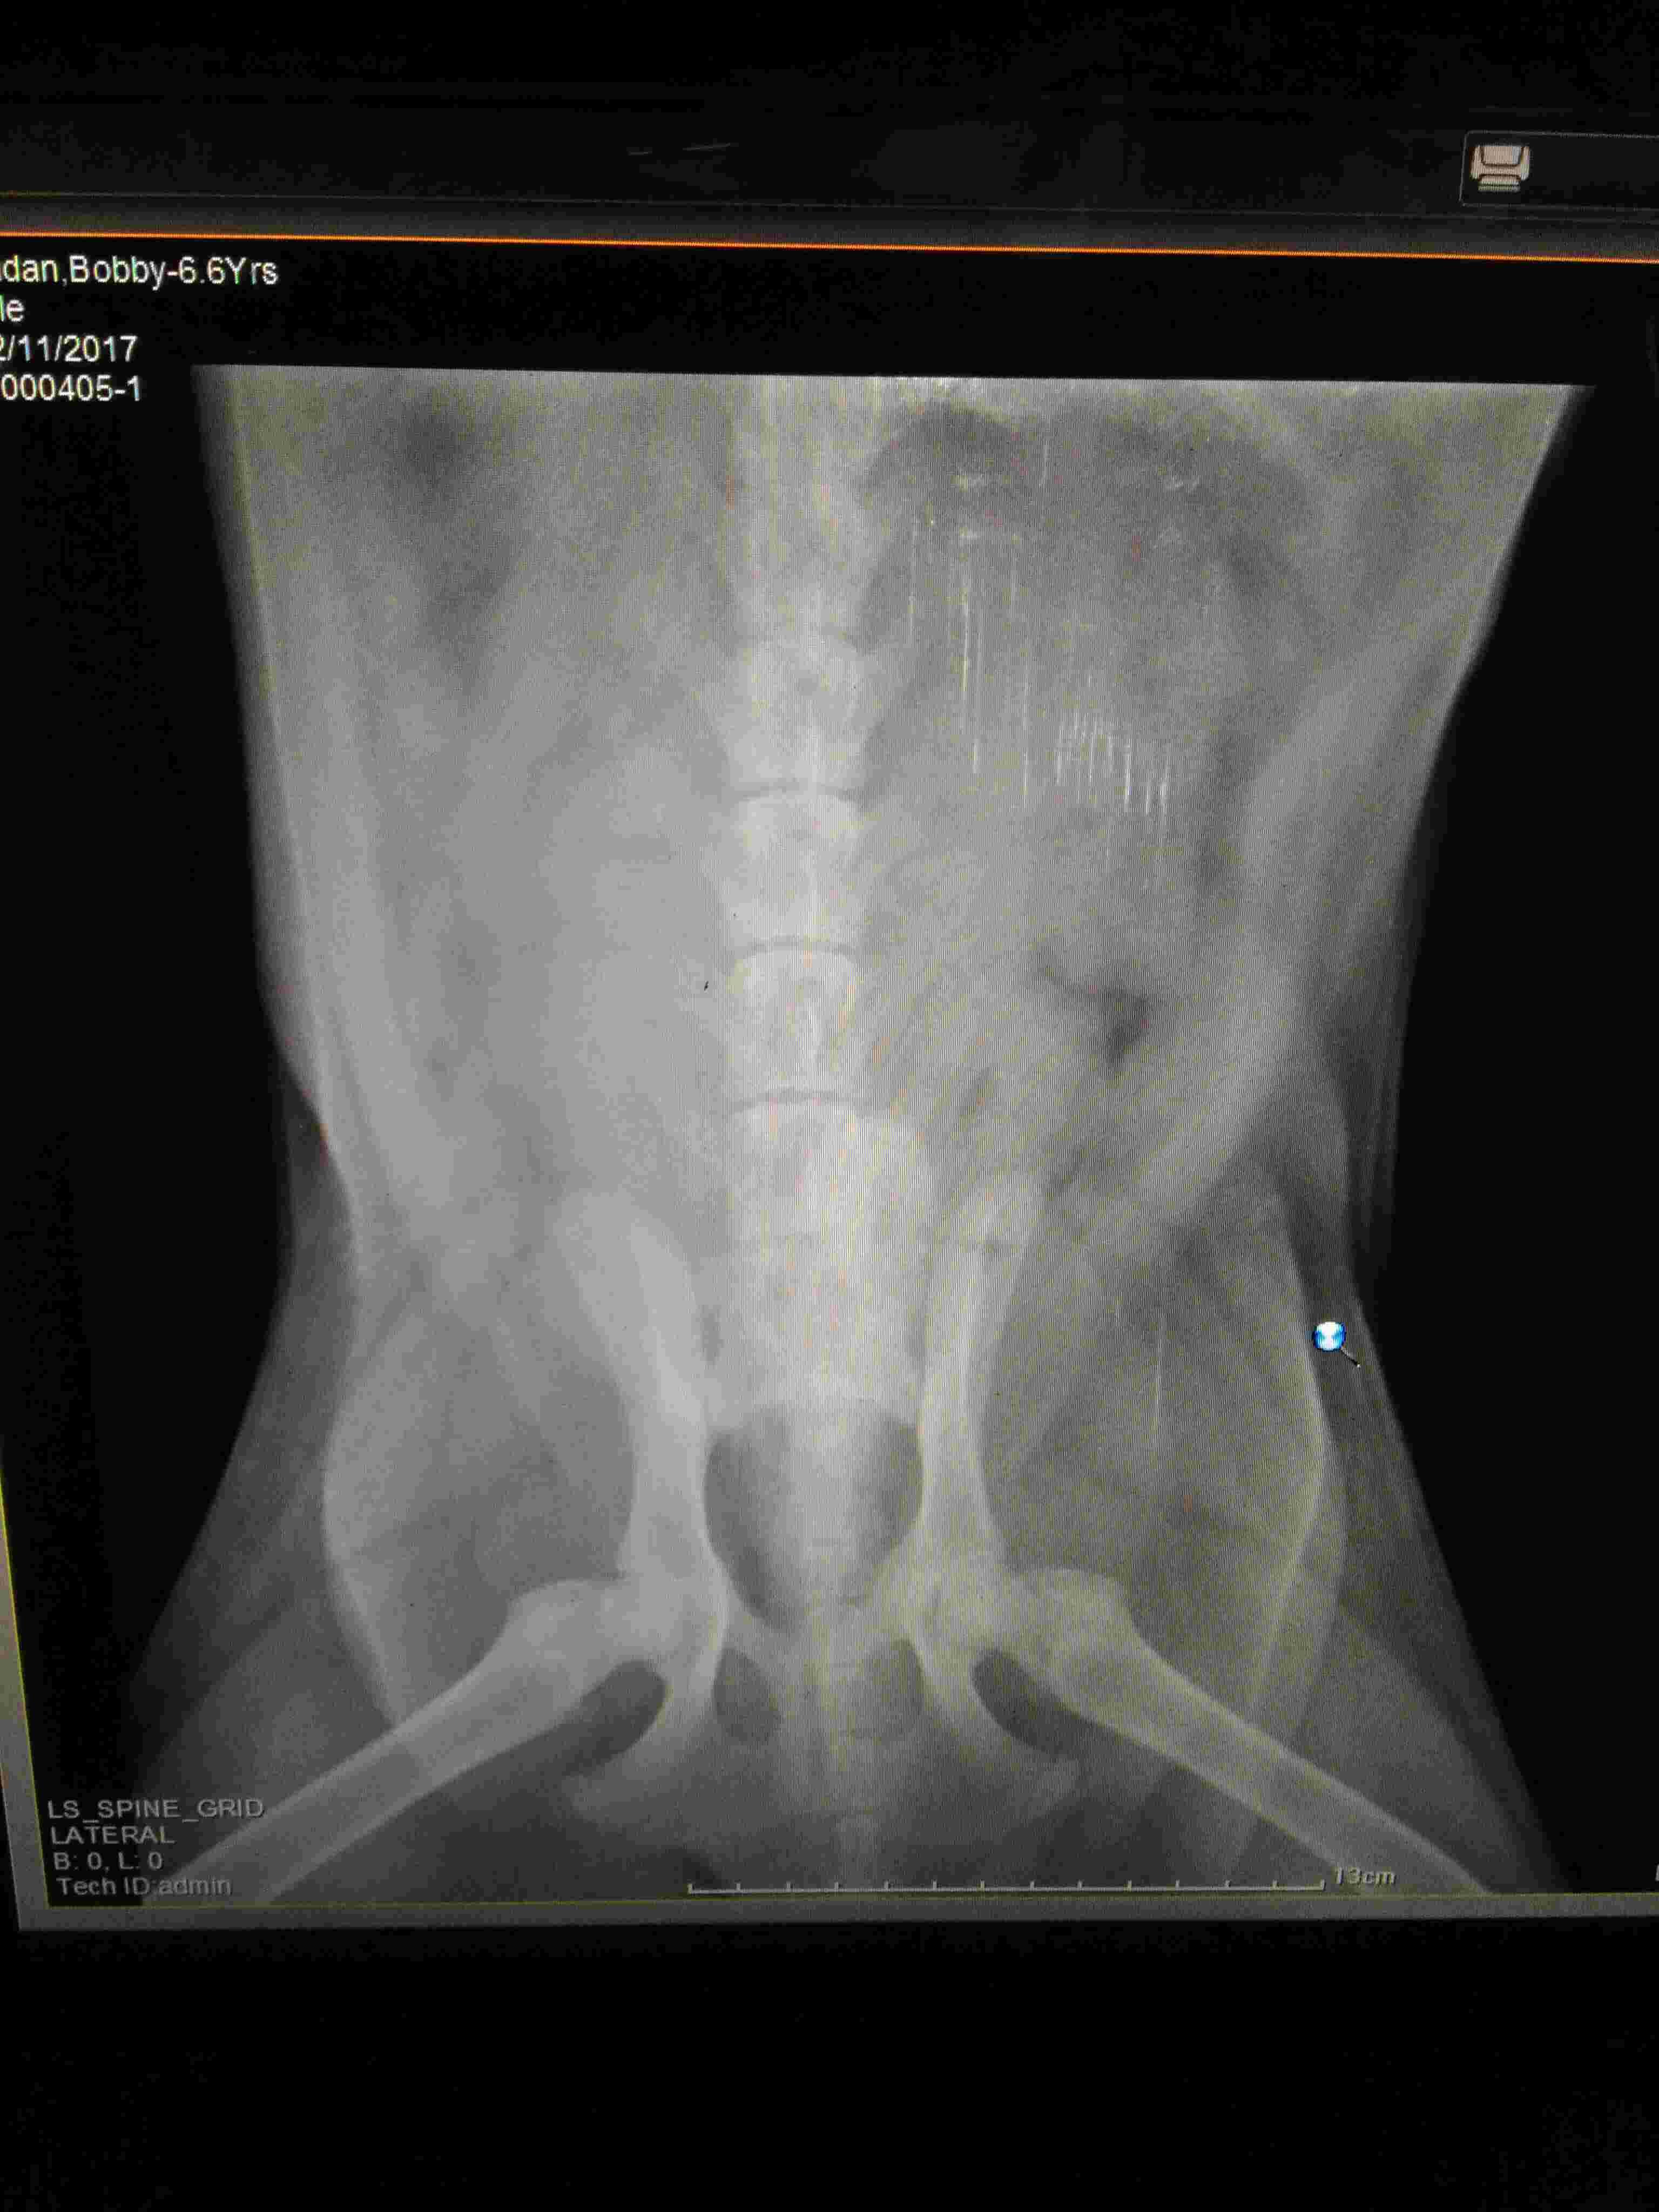

Dog fallen 20 feet on back bone he lost sense back two legs there is no fracture in bone but doc said no chance recover because spinal nurvous system damage i uoload xray pic tell me what to do with it how to recover i cant not get what to do hiw to recover him from this

I am so sorry that this has happened to Tommy. Unfortunately I cannot not say for sure if there is any chance of recovery from just X-rays. An MRI or CT really needs to be done to get the best view of the spinal cord and his intervertebral disks. Also, you may want to see if there is a veterinary surgeon who is comfortable with back surgery as this could be an option for Tommy. If not, the only other suggestion would be high doses of steroids. None of these options are guaranteed to work but they might. I hope this helps and hope that Tommy is capable of healing. Hang in there and good luck.